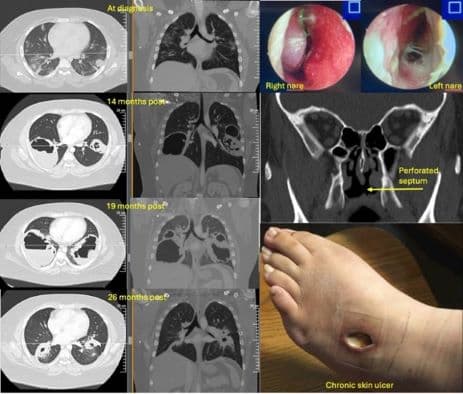

The ACR seeks images representing a diverse range of patients that show either educational or remarkable manifestations of the rheumatic disease in the following categories:

- Adult and pediatric auto-inflammatory conditions